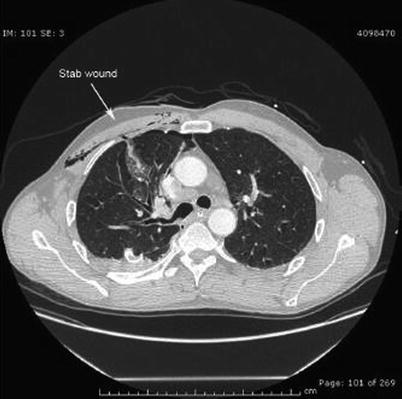

Fig. 16.4

Stab wound to the right chest with intrathoracic penetration and lung injury. No evidence of mediastinal or intrathoracic vascular injury. Successfully treated with thoracotomy tube drainage